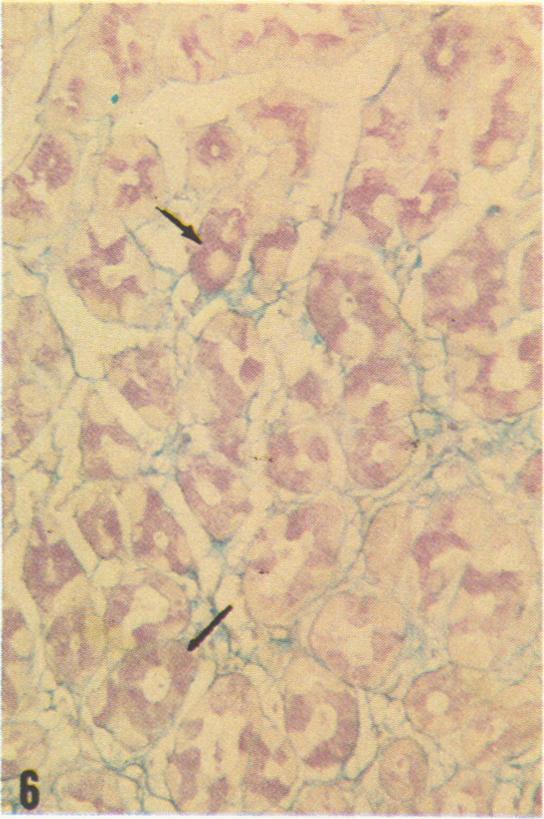

The several types of epithelial cells in human gastric mucosa produce different mucosubstances. The surface epithelium largely forms a neutral mucosubstance except that in about two-thirds of the specimens the deep foveolar cells produce a slight to moderate amount of a mucosubstance apparently containing sulfate esters and carboxyl groups. Mucous neck cells often exhibit a neutral mucosubstance but in about onehalf of the stomachs reveal a slight to moderate reactivity indicative of sulfated mucosubstance. Chief cells contain a sulfated mucosubstance with unique histochemical properties. Mast cells vary widely in prevalence but those in the gastric mucosa appear depleted of stored mucosubstances when compared with those in the gastric submucosa or the esophagus. The sulfated mucosubstance normally abundant in human as in canine chief cells appears consistently depleted in patients with stress ulcer or hemorrhagic gastritis. In addition, mucus often appears depleted in the surface epithelium and interstitial edema is present in the superficial mucosa of these patients. These findings appear consistent with the view that biosynthetic activity in chief cells and surface epithelial cells is impaired perhaps secondary to shock-induced circulatory changes in gastric mucosa of patients with stress ulcer or hemorrhagic gastritis.